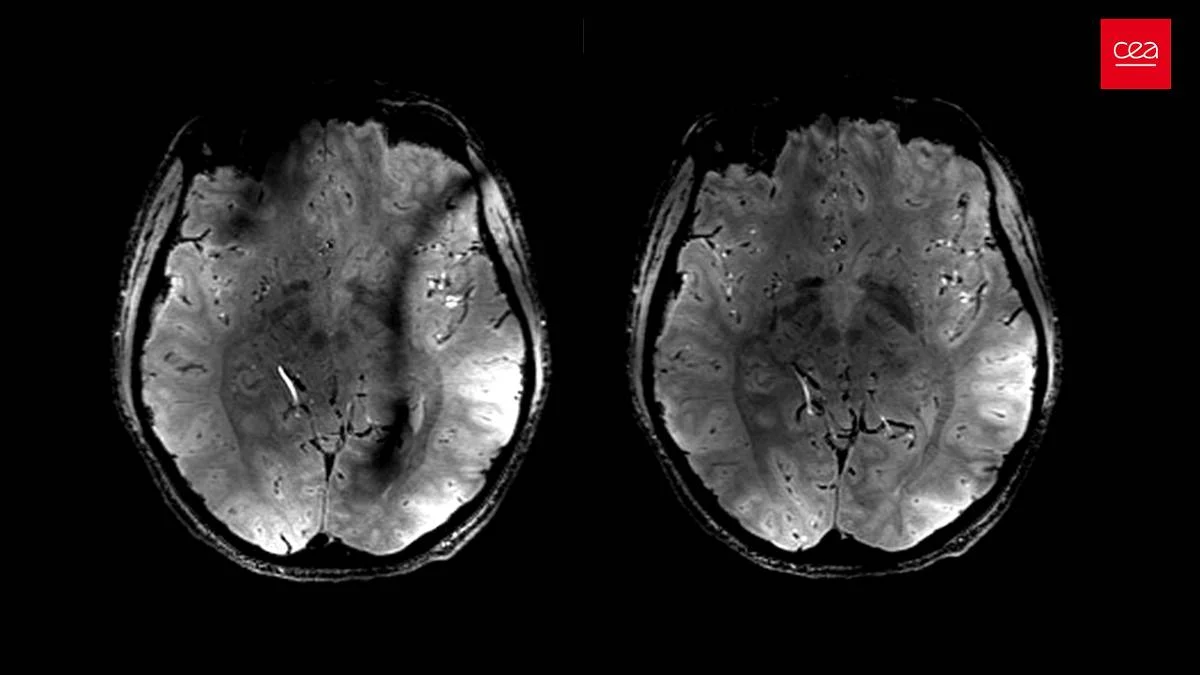

A investigação, que será apresentada na próxima semana no encontro da Radiological Society of North America (RSNA), recolheu dados de quase 3.000 doentes, incluindo tomografias computorizadas (TAC) às glândulas suprarrenais, questionários sobre stress, níveis de cortisol e outros dados de saúde que podem indicar stress prolongado.

As glândulas suprarrenais são responsáveis por produzir e regular hormonas que controlam o metabolismo, o sistema imunitário, a pressão arterial e as respostas ao stress. Os investigadores descrevem-nas como um “barómetro biológico” para medir o stress no organismo.

Os doentes que reportaram stress antes do estudo apresentavam maior volume suprarrenal, juntamente com níveis mais elevados de cortisol e risco acrescido de insuficiência cardíaca.